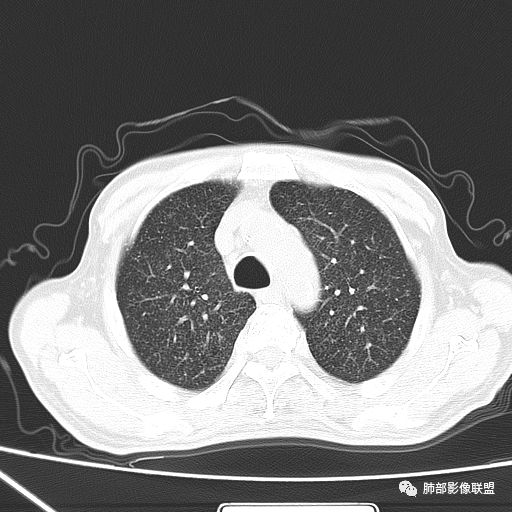

2019年9月12日CT(外院片,手机拍摄)

2019-10-20复查CT如下:

两肺弥漫性粟粒样结节伴左上肺小结节,呈三均匀分布,有结核的临床表现,支持血性播散性肺结核。

大小、分布均匀,边缘清楚

细小结节,弥漫,撒米粒样——血道来源

部分可见分支状

边缘稍平直

毛刺细弱

还是支持结核

血道来源的病灶,均匀、细微,而且部分有分支状,都符合粟粒型肺结核

急性血行播散型肺结核  两肺广泛分布粟粒大小的结节状密度增高影,具有大小均匀、分布均匀、密度均匀的典型“三均匀”特征,注意急性血播病灶非常小,一般粟粒影直径1~2mm。

病灶密集者出现肺外围血管影不清或减少。

发热初期肺部可缺乏典型影像学改变,1到2周后出现的广泛粟粒结节对诊断具有高度提示作用!